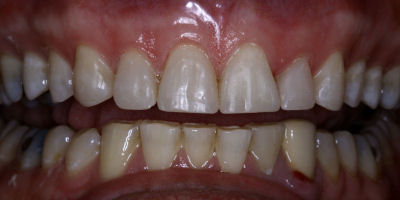

Before/After

Closing Spaces

Opening Bite

Repair Worn Teeth